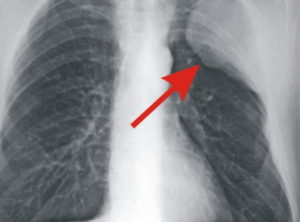

— Я задал вопрос онкологу, как можно пройти флюорографию и медкомиссию и не обнаружить онкологию на такой стадии? Мне ответили: на снимке тень сердца, не смогли увидеть.

При этом следователями было установлено, что за несколько месяцев до постановки диагноза врач-рентгенолог не обнаружила на снимке легкого и сердца видимой патологии.

Сыну умершего Александру Шкреду заключение комиссии без письменного запроса также не предоставили. Устно пояснили, что комиссия врачей на июльском снимке не нашла отклонений.

Лишь специально приглашенный врач-онколог разглядел некую патологию, которая к раку не имеет отношения, передает слова медиков собеседник.

Видно ли рак легких на флюорографии или нет? Данный метод исследования не позволяет точно определить злокачественную опухоль, а позволяет лишь увидеть само новообразование. Врач делает снимки в прямой проекции. При необходимости делают боковые снимки, что позволяет определить какой именно рак:

Так показывает ли флюорография рак? Да, рентгеноскопия позволяет увидеть врачу рентгенологу затемнение или просветление, контуры, полости новообразования. Да и сам пациент может просмотреть рентген и увидеть, так как чаще всего четко просматриваются заболевания органов дыхания.

При центральной форме ракового образования, на рентгенографии будет отображаться, что в легких присутствует расширенная сеть сосудов, а также имеются замутненные участки. Когда у легочной онкологии периферический характер, картина на рентгеновском изображении будет отображать присутствие четкой тени с неровными краями, от которой к корню легких отходят отростки в виде лент.

Флюорография выявляет рак легких? Да, но, к сожалению, не во всех случаях. Это связано с серьезным недостатком методики — процедура проводится только в прямой проекции. Поэтому существует ряд факторов, когда при флюорографии не удается распознать опухоль в легких:

- Новообразование находится в базальных сегментах нижней правой доли органа. Так как их загораживает печень, рассмотреть опухоль специалисту не представляется возможным.

- Слишком мелкие онкологические очаги.

- Опухоль расположена слишком глубоко в тканях органа.